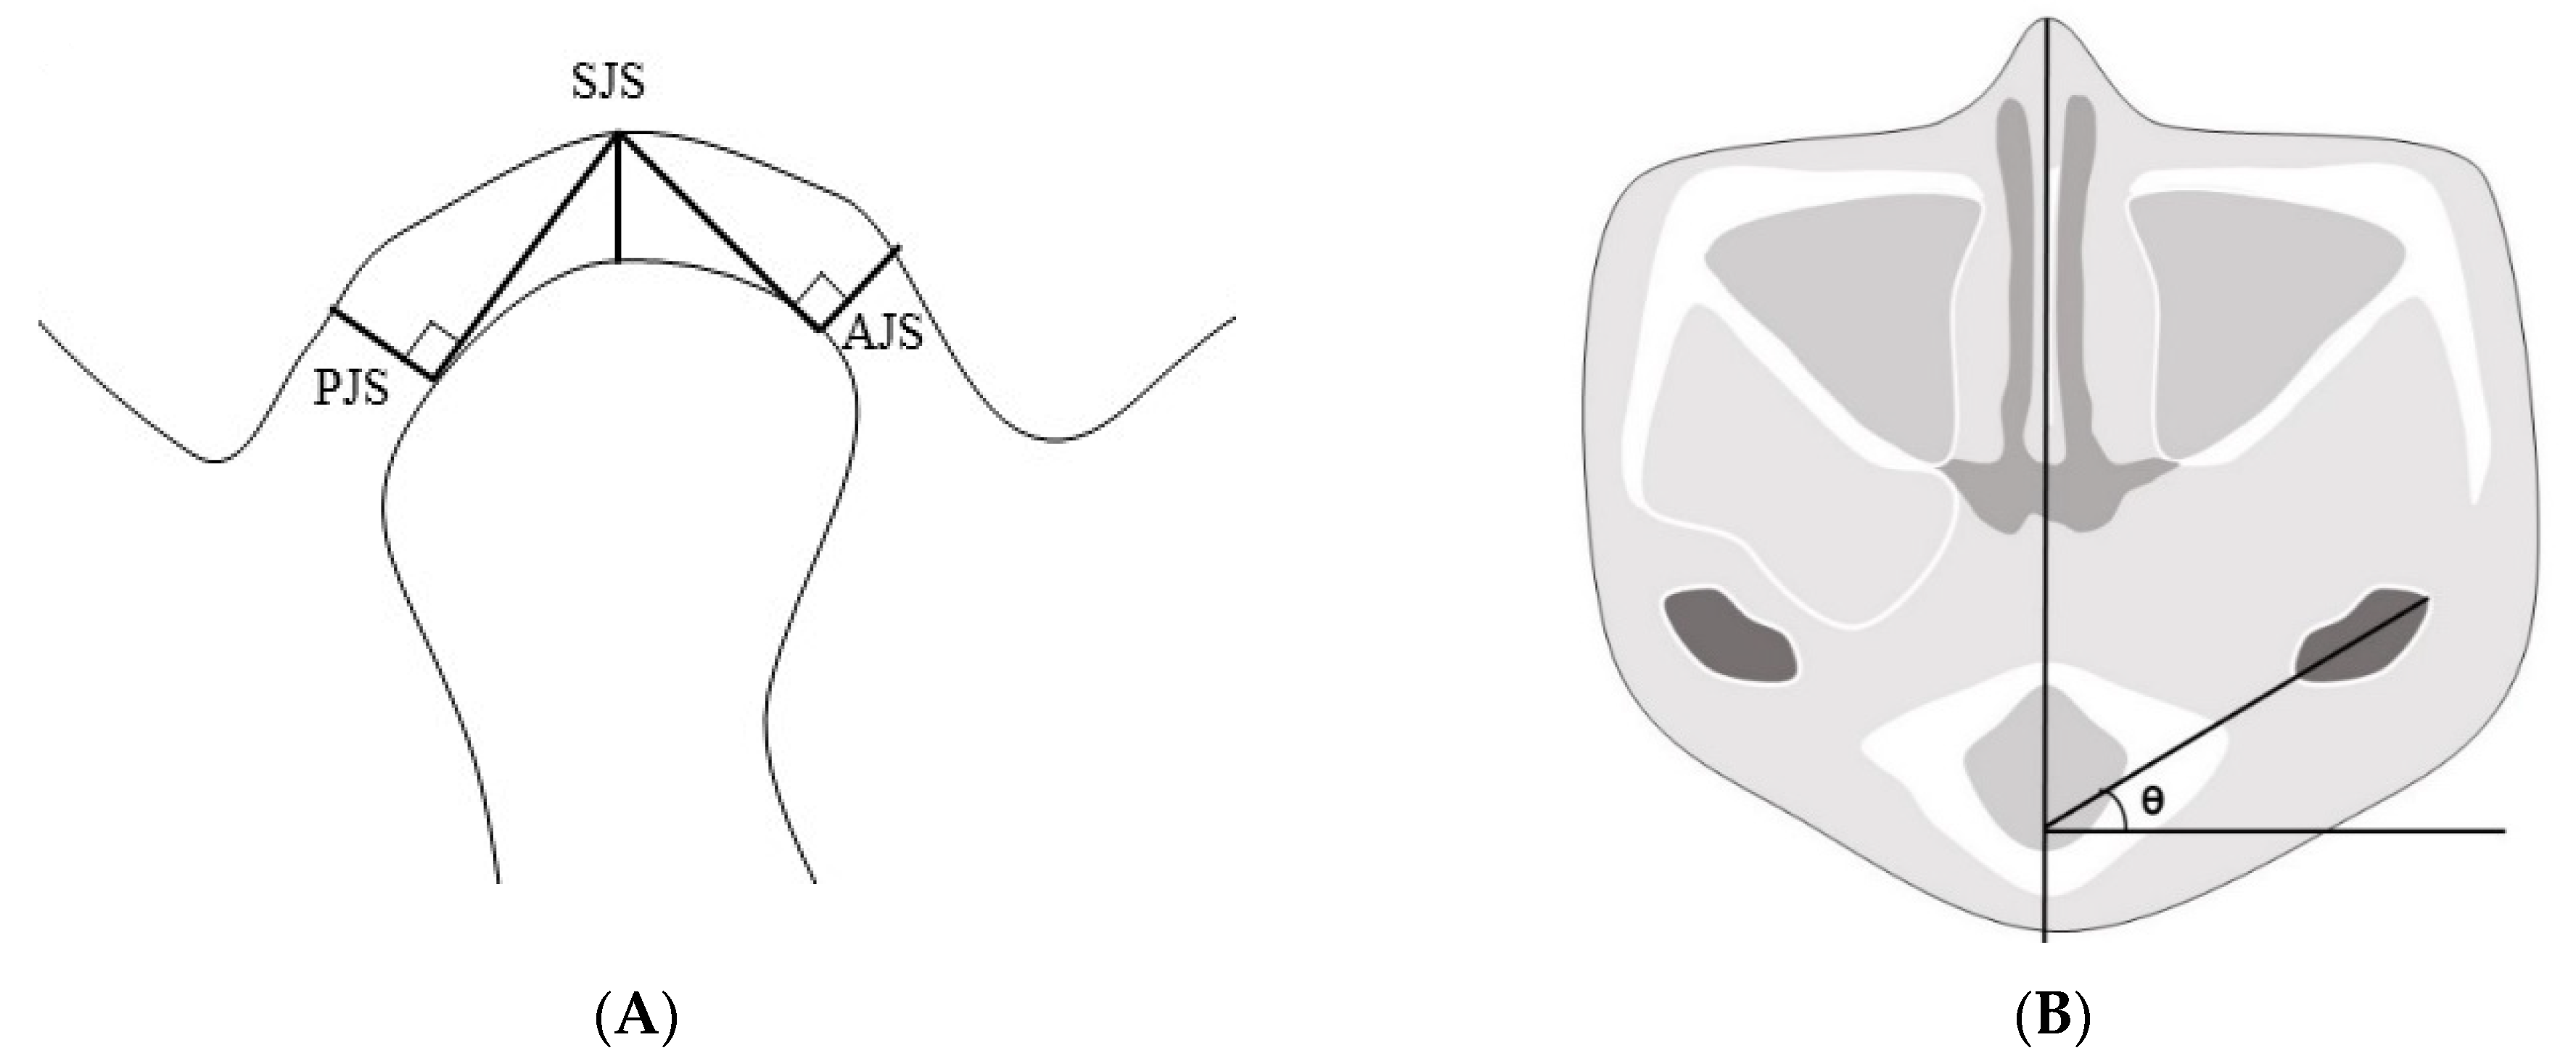

We chose a plane of reference at the left external carotid canal in the axial view, which was a line from the innermost point to the outermost point of the condyle parallel to the sagittal plane. After that, we set a plane perpendicular to the line at its midpoint. The superior joint space (SJS) was defined as the distance measured from the top of the condyle to the deepest point of the glenoid fossa in the plane. Tangent lines were drawn to the most prominent points on the condyle’s anterior and posterior aspects from the deepest point of the glenoid fossa. The anterior joint space (AJS) was defined as the perpendicular distance between the most prominent point on the anterior aspect and the glenoid fossa. The posterior joint space (PJS) was defined as the perpendicular distance between the most prominent point on the posterior aspect and the glenoid fossa. The angle of the condyle or the condylar angle was defined as the angle between the line from the innermost point to the outermost point of the condyle parallel to the sagittal plane and the sagittal plane (Figure 4).

Figure 4.

(A) The plane of reference in the axial plane at the left external carotid canal with lines from the innermost and outermost points on the condyle. Reference plane perpendicular to the line at the midpoint. Anterior, superior, and posterior joint spaces in the plane (AJS, SJS, and PJS, respectively). (B) The angle of the condyle was defined as the angle between the line from the innermost point to the outermost point of the condyle parallel to the sagittal plane and the sagittal plane. AJS: anterior joint space; SJS: superior joint space; PJS: posterior joint space.